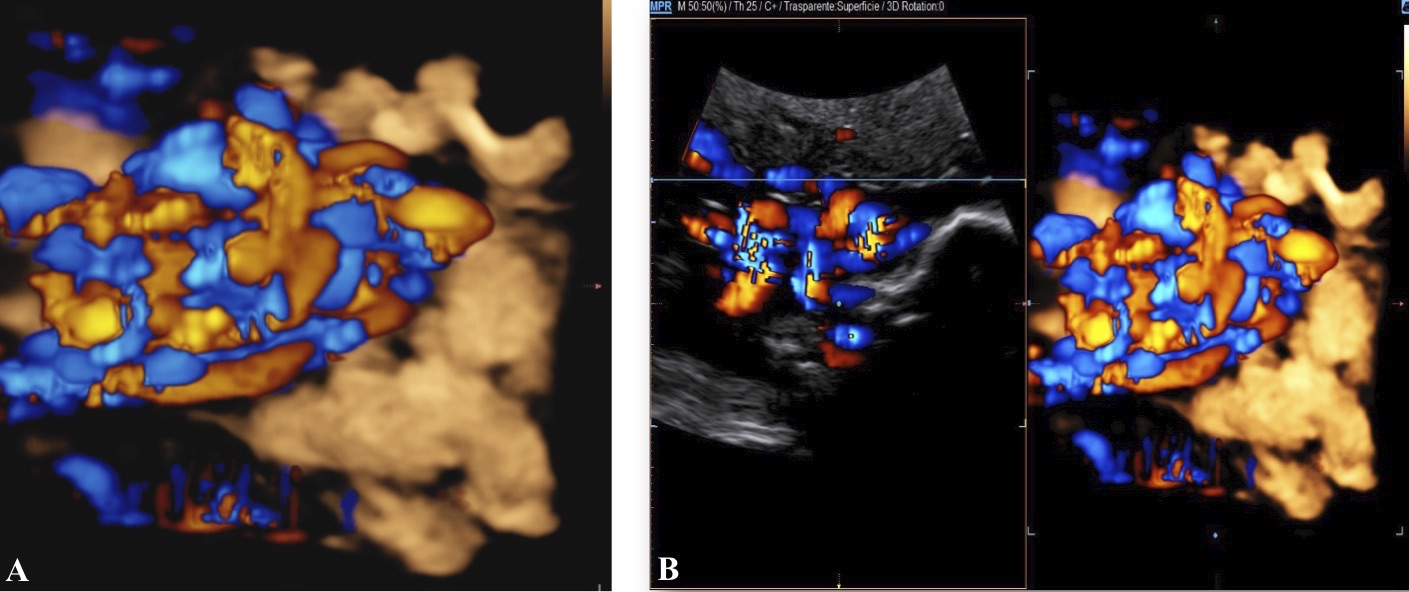

A healthy 39-year-old woman G4P3 was admitted to our high-risk pregnancy outpatient service due to a MC-DA twin pregnancy. Monochorionicity was suspected by the referring gynecologist during the dating ultrasound scan (US). The nuchal translucency US at the 12th week of gestation highlighted a “T” sign of the dividing membrane with a unique anterior placenta confirming a MC-DA twin pregnancy, as shown in Fig. 1. Soft markers for trisomy were found to be normal for both twins. The US performed during the 14th week of gestation showed the twins significantly closer to each-other standing on the same side of a free-floating thin membrane inserted on the placenta. This image raised the suspicion for a spontaneous septostomy (Fig. 2). The patient underwent amniocentesis as the combined serum screen showed an increased risk for Trisomy 21. US assisted invasive procedure did not detect the dividing membrane deposing for a PMM twin pregnancy following SS. A single sample of amniotic fluid was obtained and tested normal for fetal karyotype (46, XX). According to International Guidelines US imaging was performed every two weeks. Anomaly scan was normal and all subsequent Doppler US showed a normal twin growth and fetal wellbeing until the early third trimester [14, 15, 16]. The US performed at the 27th week of gestation showed a strict contiguity of the umbilical cords with a suspicion for cord entanglement on 3-dimensional (3D) US (Fig. 3A,B). The patient was hospitalized for close pregnancy surveillance. Fetal heart monitoring and US scan were daily performed. Steroids were administered for prevention of respiratory distress syndrome. The 29th week US scan highlighted a growth discordance ranging around 21% (symmetric growth at the 71° centile (estimated weight: 1328 gr) and at the 36° centile (estimated weight: 1043 gr) for Twin A and Twin B respectively). An episode of prolonged bradycardia was registered for Twin A. An emergency cesarean section was performed: two healthy girls were born (Twin A: weight 1360 gr, Apgar 4 and 7 at 1st and 5th minute respectively — Twin B: weight 1000 gr, Apgar 8 and 9 at 1st and 5th minute respectively). Cord entanglement was confirmed as shown in Fig. 4. The mother’s postoperative recovery was uneventful. Twins’ developmental follow-up at 12 months of age was normal.

Fig. 3.Sonograms depicting 3-dimensional imaging of cord entanglement suspected during the 27th week US.